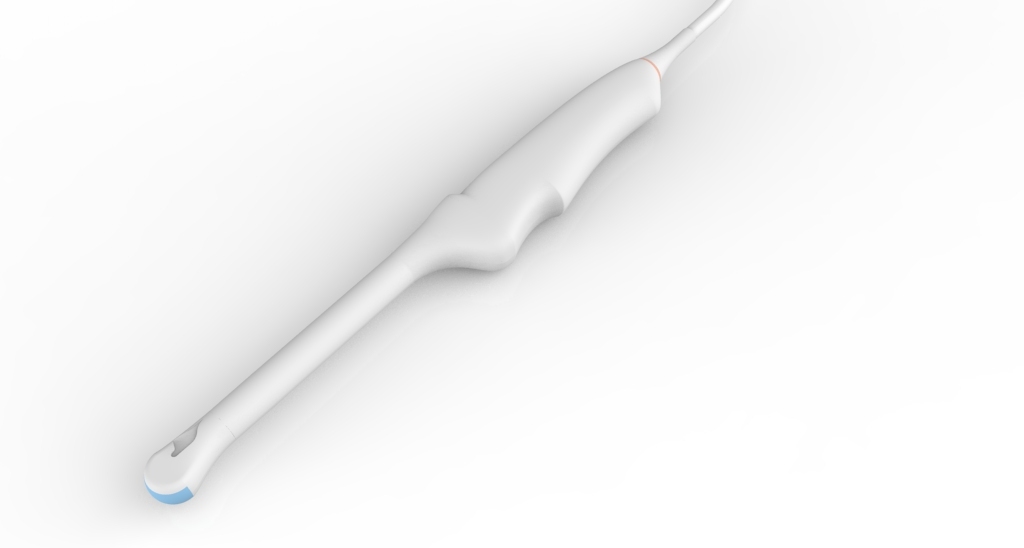

Внутриполостной E8-4QL17-7Q

Внутриполостной E8-4Q

Трансвагинальный E8-4D

Трансвагинальный E612UB